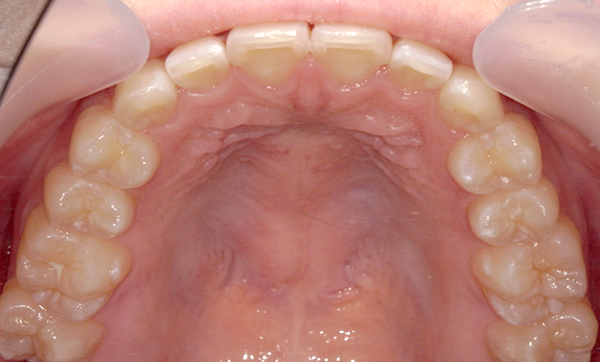

症例_009 「上下の前歯」症例

治療期間:7ヶ月金額:54万円+税20代女性捻転歯一部の反対咬合前歯のガタガタ